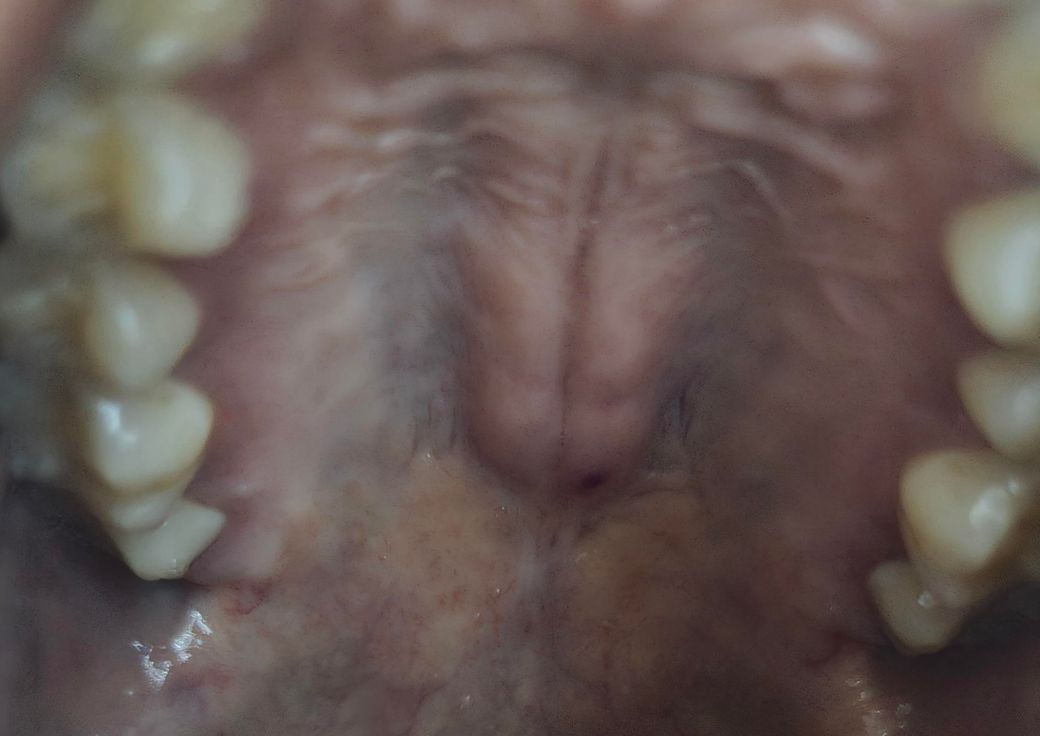

입천장에 뭔가 딱딱하게 부어올랐어요

저 검은 점은 상처입니다. 이비인후과에서 아무말씀없고 약처방하고 소독만 해주셨는데 무서워서 질문올려요. 그냥 뭔가에 찔린느낌만 들고 목구멍은 간질간질 기침 조금씩나와요 어제 야키토리 먹긴했는데 찔린기억은 없는거같습니다

입천장에 딱딱하게 부풀어 오른 것이 단순한 염증일 수도 있지만, 정확한 원인을 파악하기 위해서는 좀 더 자세한 정보가 필요합니다. 이비인후과에서 약을 처방받고 소독만 받으셨다면, 염증이 생긴 부위가 작은 상처나 자극으로 인한 것일 수 있습니다. 야키토리나 음식을 먹을 때 의도하지 않게 상처를 입었거나, 음식물 찌꺼기가 박혀서 염증을 일으킬 수도 있구요. 기침과 간질간질한 느낌은 입천장의 염증이나 자극으로 인해 생길 수 있는 증상들이죠

하지만 만약 부어오른 부분이 점점 커지거나 통증이 심해지거나, 다른 불편한 증상이 나타나면 다시 이비인후과를 방문하거나 다른 전문의에게 진료 및 검사를 받는 것이 좋습니다.